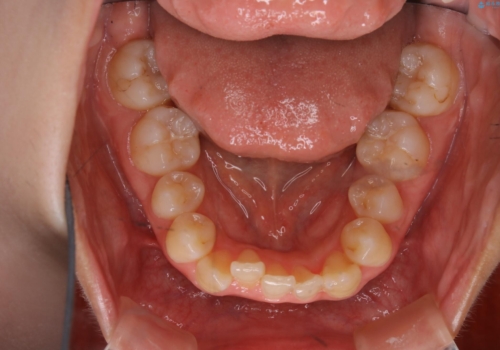

元々下の前歯が1本欠損しており、上下の噛み合わせや、歯のサイズバランスを考慮しながら治療を行いました。

下顎切歯が1本欠損しているため、上顎前歯部を少しずつストリッピングして、上下の噛み合わせ、バランスの向上を図りました。